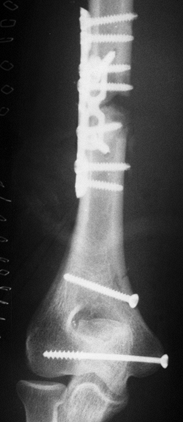

Grade II open, severely comminuted pylon fracture of the left ankle involving the tibia and fibula (Fig. 14.6).![]() Figure 14.6. Comminuted pylon fracture of the left distal tibia and fibula. Figure 14.6. Comminuted pylon fracture of the left distal tibia and fibula.

the medial condyle fracture was fixed with two interfragmentary screws (Fig. 14.8). The midshaft fractures of the left radius and ulna were compression plated (Fig. 14.9).

wound, and the leg was placed in a delta-frame-type external fixator (Fig. 14.11).

| Figure 14.11. Left pylon fracture of the tibia and fibula after external fixation. |